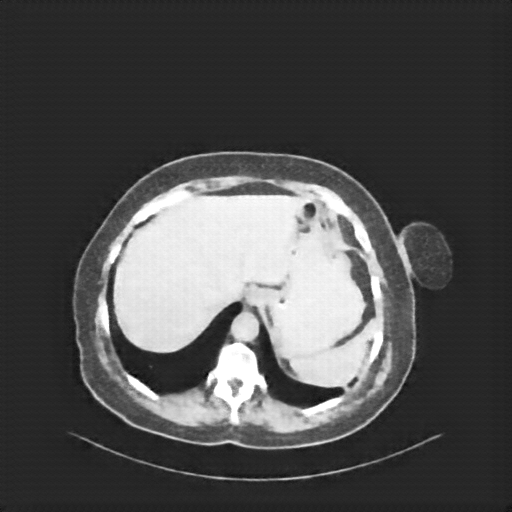

Original VENOUS CT scan

Full window (WL 1023.5, WW 4095 β†’ Low βˆ’1024, High +3071)